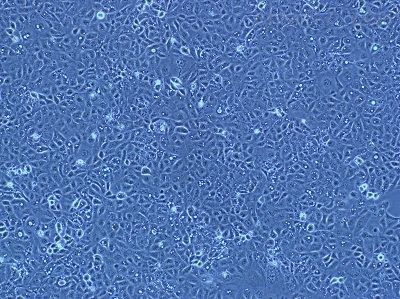

5)细胞生长方式:铺路石状细胞,不规则细胞,贴壁培养。

原代微血管内皮 细 胞( Primary Microvascular Endothelial Cells )的体外分离培养 微血管内皮细胞生长因子的应用和免疫磁珠技术的发展,使微血管内皮细胞的培养和纯化变得相对简化。 1、微血管内皮细胞培养简述人体主要器官和组织的微血管内皮细胞已经培养成功的有:骨骼肌、心、脑、胃、视网膜、肺、皮肤、脉络膜、小肠、脂肪、肝窦、肾、关节滑膜、胎盘、骨髓、胰岛、角膜及食道等器官组织的微血管内皮细胞。 2、微血管内皮细胞的分离目前分离内皮细胞的方法主要有三种